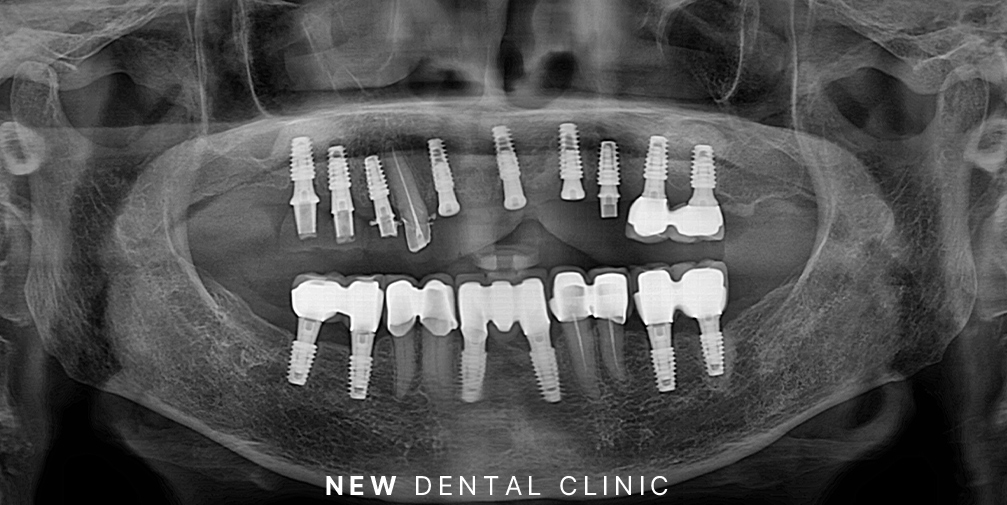

이어서 순차적으로 임플란트 식립과 보철의 과정을 마무리하였습니다.

인공치근을 잇몸뼈에 식립한 후 기존의 잇몸뼈와 단단히 융합될 수 있는 기간을 충분히 기다려준 뒤 수치가 충분한 부위부터 차례로 마무리를 진행하였습니다.

환자분께서는 보험 임플란트 적용 대상자 셔서 앞니 두 개는 보험 임플란트로 진행하셨으며 위쪽의 뼈가 약한 부분은 2차 수술의 과정까지 거친 뒤 튼튼하게 사용하실 수 있도록 마무리를 하였습니다.